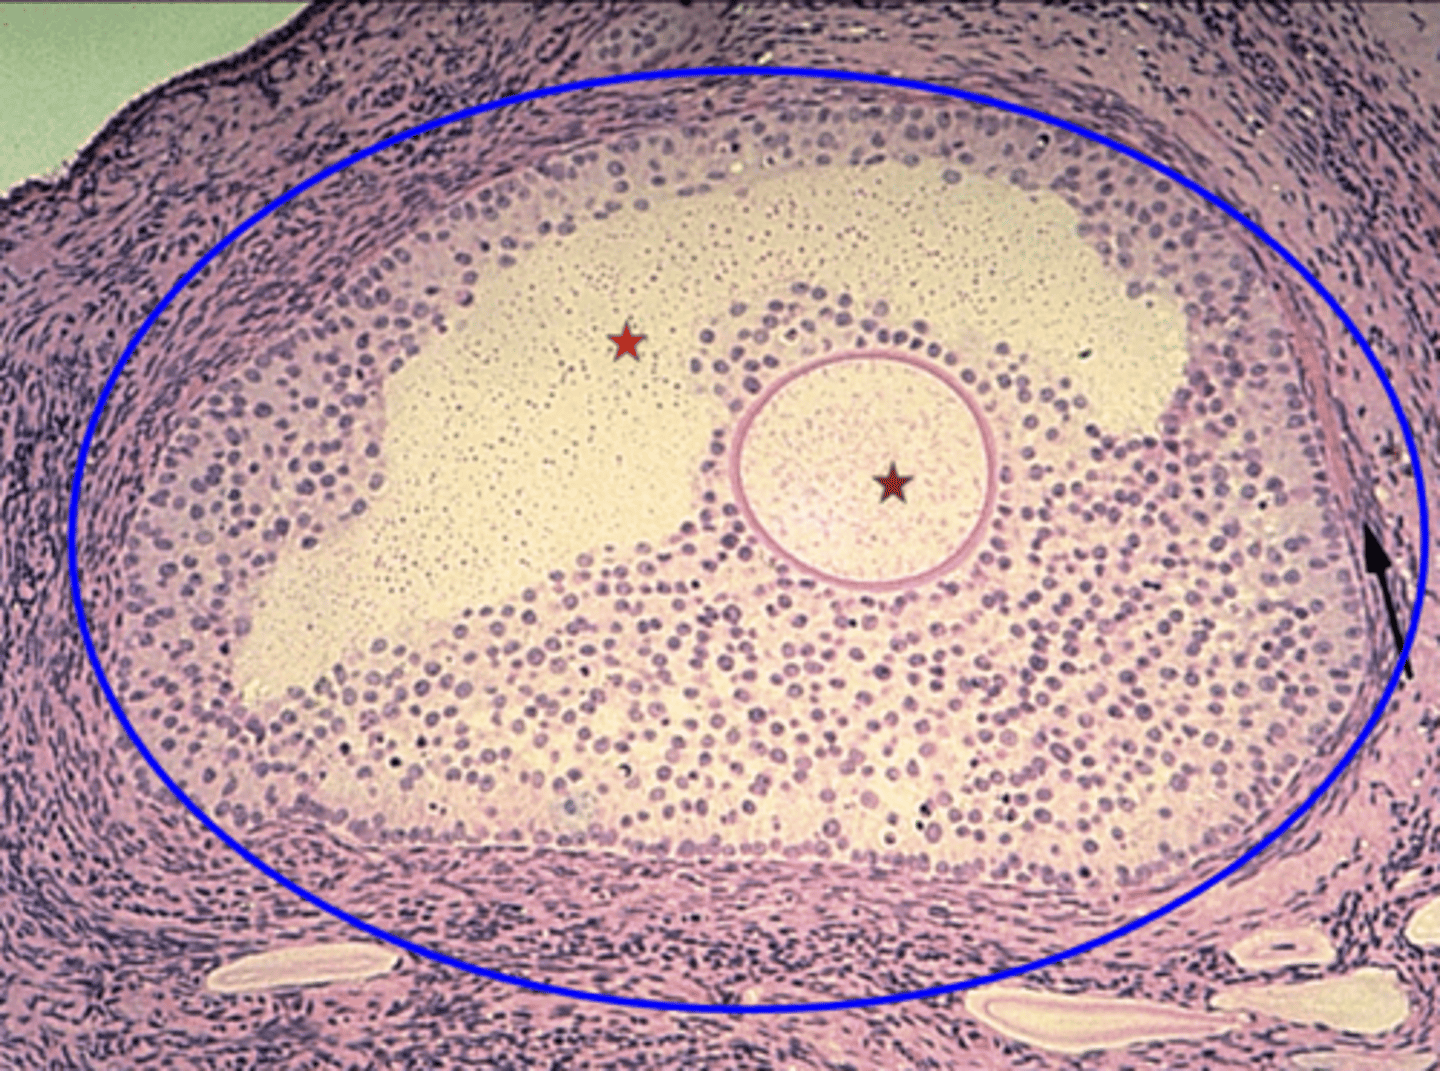

Seminiferous tubule

What is the green outline?

Spermatogonium

What is the black arrow?

Primary spermatocyte

What is the red arrow?

Spermatid

What is the blue arrow?

Spermatozoon

What is the purple arrow?

Interstitial cells

What is the pink outline?